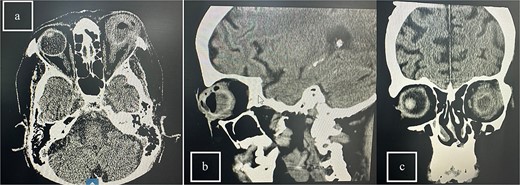

Patient 5: Fifteen days post-phacoemulsification, a 65-year-old Saudi female presented with no light perception (NPL) and severe lid edema (Fig. 9). B-scan revealed vitritis (Fig. 9). Figure 10 showing the B-Scan Ultrasound, illustrates the findings in Patient 5. Computed tomography (CT) scans of the orbit showed pan ophthalmitis (Fig. 11). She received intravitreal antibiotics immediately, followed by a pars plana vitrectomy.

CT scans of the orbit for patient 5 showing (a) coronal view with dense fluid content and air-fluid leveling, (b) axial view with edematous changes in the intra-conal fat, and (c) sagittal view with involvement of the extra-ocular muscles.